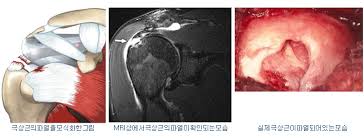

회전근개는 어깨 관절을 감싸는 네 개의 힘줄로 구성되어 있습니다. 이 근육들은 팔을 움직이고 관절을 고정시키는 데 핵심 역할을 하며, 작은 손상에도 큰 불편을 초래할 수 있습니다. 이 부위가 반복적인 자극이나 외부 충격으로 인해 찢어지면 어깨 회전근개 파열 원인에 해당하는 상태가 되는 거예요.

초기에는 단순한 통증이나 뻐근함 정도로 느껴지기 때문에 대수롭지 않게 넘기기 쉬워요. 하지만 증상이 지속되거나 악화된다면 어깨 회전근개 파열 원인을 분명히 확인해야 합니다. 진단은 초음파, MRI 검사를 통해 가능하며, 근육이나 힘줄의 파열 여부, 크기, 위치 등을 정밀하게 확인할 수 있습니다.